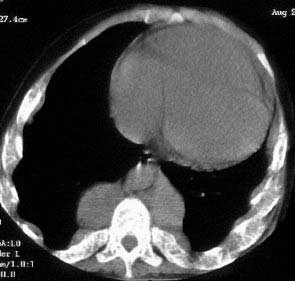

以下是引用hfs999999在2004-12-10 21:07:44的发言:[br]地中海贫血伴髓外造血可能,须於骨纤鉴别

以下是引用jiajie在2004-12-10 22:14:53的发言:[br]多发性肋骨骨质疏松,[br][br]麦粒状及筛孔状骨质破坏,[br][br]髓腔膨胀皮质变薄,[br][br]骨旁多发软组织肿块,[br][br]考虑恶性病变,支持肋骨多发性骨髓瘤。

以下是引用pujunzhi在2008-7-3 21:21:00的发言:[br]支持地中海贫血伴髓外造血可能性大,需与多发性骨髓瘤、淋巴瘤等鉴别。